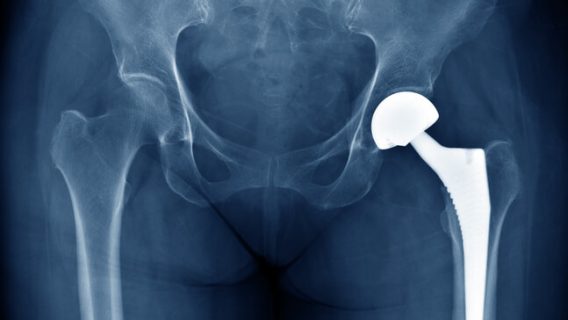

Zimmer Loses $9.2M to Man in Durom Hip Implant Verdict

A Michigan Man’s Battle With Cobalt Poisoning After Metal-on-Metal Hip Implants